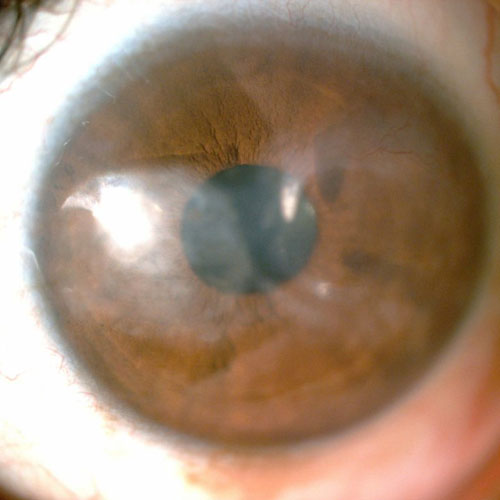

Dr. Abdul Rasheed, one of the leading Ophthalmologist and Cataract & Refractive surgeon in the city of Hyderabad provides extensive and comprehensive care for all your eye sight issues. Vision disturbance are one of the few issues which have the capacity to completely disturb our daily life and activities. Correcting them in the right way to avoid further complications or risk is the motto of Dr. Abdul Rasheed. With age comes cataract, Dr.Rasheed is an expert in complicated cataracts such as small pupil, zonular dialysis, mature / Brunescent cataracts, corneal scars, shallow Ac, etc., as well as complicated refractive surgery cases like RK scars, corneal scars, etc. While coming to refractive surgeries, Dr. Abdul Rasheed strongly believes and says "Any patient irrespective of complexity, who can be refracted to 6/6 can be treated to read the same without glasses." He has treated many patients of keratoconus who had extreme distortion of vision. After INTACS implantation followed by ICL, patients were able to regain normal vision.